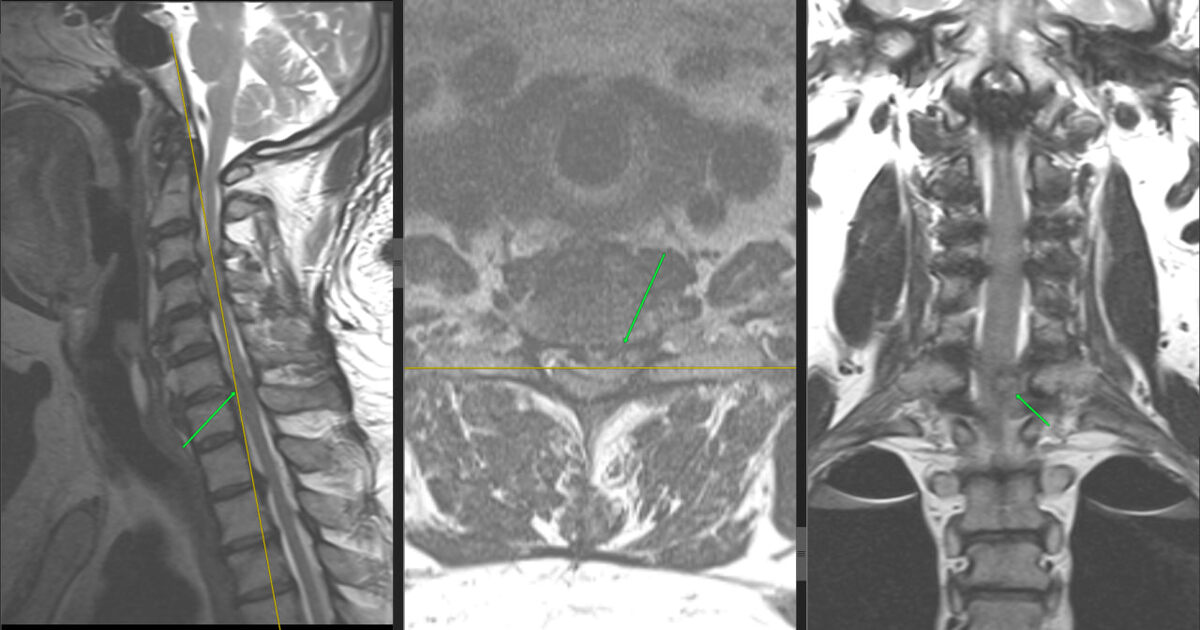

КТ показала: шея будто зацементирована — все суставы срослись, связки превратились в кость (анкилоз + оссификация).

МРТ подтвердила: диск С6-С7 разорван, грыжа давит на спинной мозг и нерв.

Диагноз: Травматический разрыв диска с ущемлением нервов.